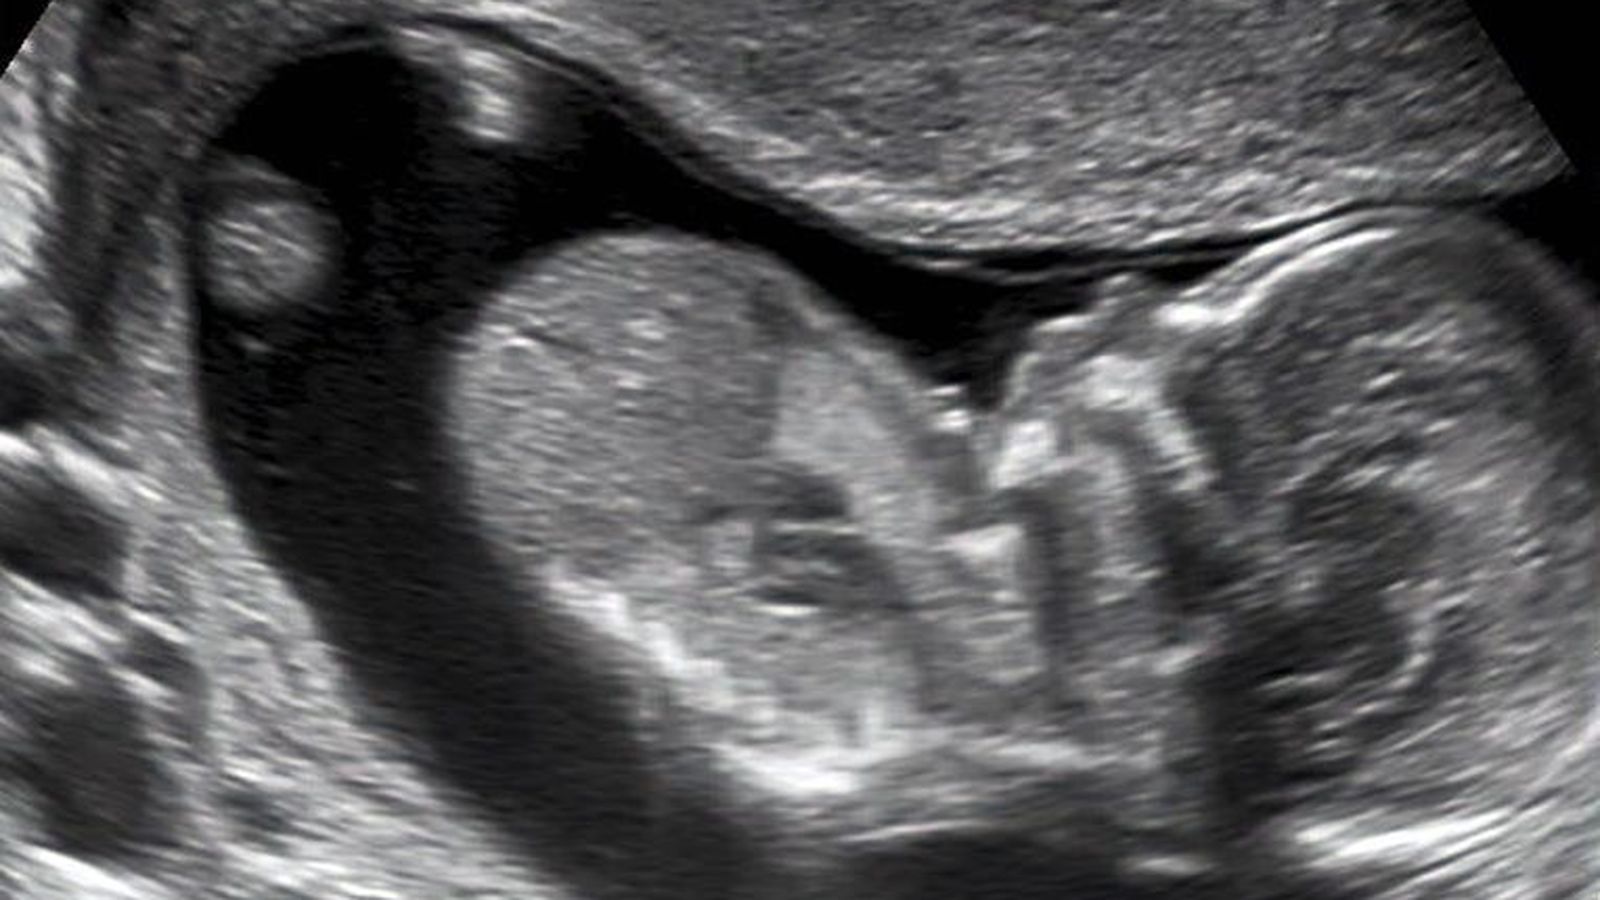

Imagen ecográfica del primer trimeste de gestación.

Imagen ecográfica del primer trimeste de gestación. / M.G.